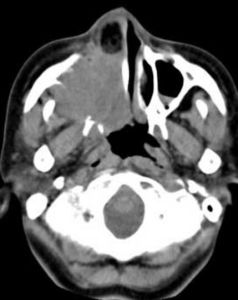

影像症狀

嗅神經母細胞瘤X線特點包括"亞鈴形"腫塊,腫物延伸穿過篩板。病變範圍在MRI的T1加權像和在T1加權像基礎上注射釓標記增強後的T2加權像的前後對比中可非常好的顯示出來。骨侵蝕的細微改變(紙樣板,篩板和篩凹)在CT掃描中能很好顯示,在X線片中可見鈣化引起的斑點狀形態。血管造影可發現病變為血管增生性腫瘤。

嗅神經母細胞瘤的X線特點包括“啞鈴型”腫塊,腫物延伸穿過篩板,病變範圍在MRI的T1加權像和T2加權像的前後對比中科非常好的顯示出來。骨侵蝕的細微改變(紙樣板、篩板和篩凹)在CT掃描中能很好顯示,在X線片中可見鈣化引起的斑點狀形態。血管造影可發現為血管增生性腫瘤。